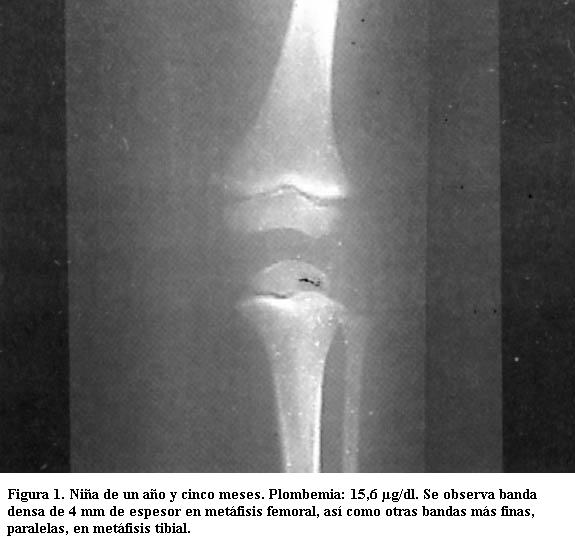

Son visibles radiológicamente cuando la absorción del tóxico se ha mantenido durante varios meses (figuras 1 y 2) (4).

Tienen varios milímetros de espesor y sus límites son nítidos. Son tanto más densas cuanto mayor sea el grado de absorción del metal y tanto más anchas cuanto más haya durado el proceso de absorción (figuras 3, 4 y 5) (5).

Predominan en las de crecimiento más rápido (las ubicadas en rodillas y muñecas) incluido el peroné, signo de importancia ya que otras enfermedades que producen bandas densas metafisarias no afectan este hueso (3).